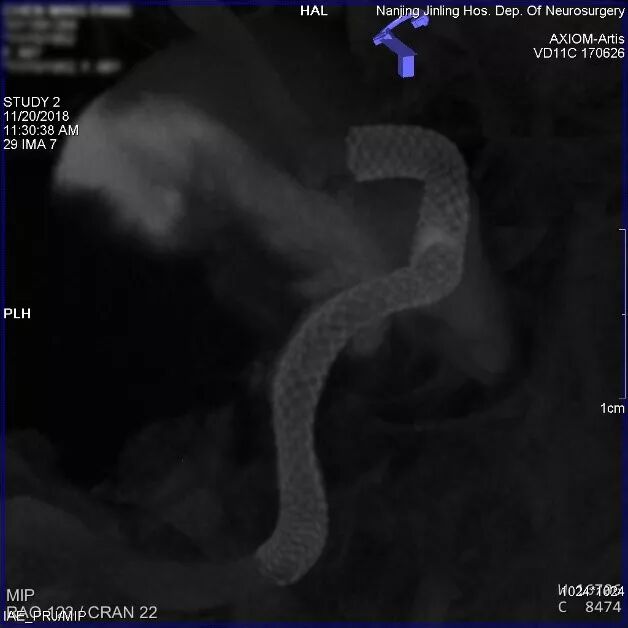

最后造影显示载瘤动脉通畅,瘤内血流有滞留。3D重建示支架贴壁良好。

为什么要用到微导管张鑫教授:“球囊锚定微导管辅助到位”技术在Pipeline Flex治疗复杂动脉瘤手术中的应用_https://www.jmylbn.com_新闻资讯_第12张

支架释放后造影,瘤内血流明显减缓,造影剂滞留

为什么要用到微导管张鑫教授:“球囊锚定微导管辅助到位”技术在Pipeline Flex治疗复杂动脉瘤手术中的应用_https://www.jmylbn.com_新闻资讯_第13张

为什么要用到微导管张鑫教授:“球囊锚定微导管辅助到位”技术在Pipeline Flex治疗复杂动脉瘤手术中的应用_https://www.jmylbn.com_新闻资讯_第14张

3D重建示支架全程贴壁良好